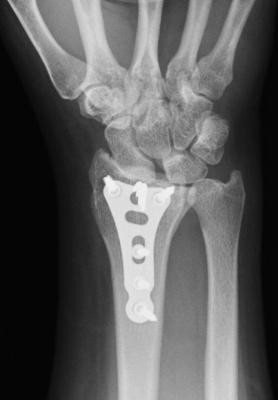

Auswärts versorgte Radiusfraktur.

Man glaubt der Befund sei eindeutig. Wenn man genau hinschaut, sieht man wo das wirkliche Problem liegt.